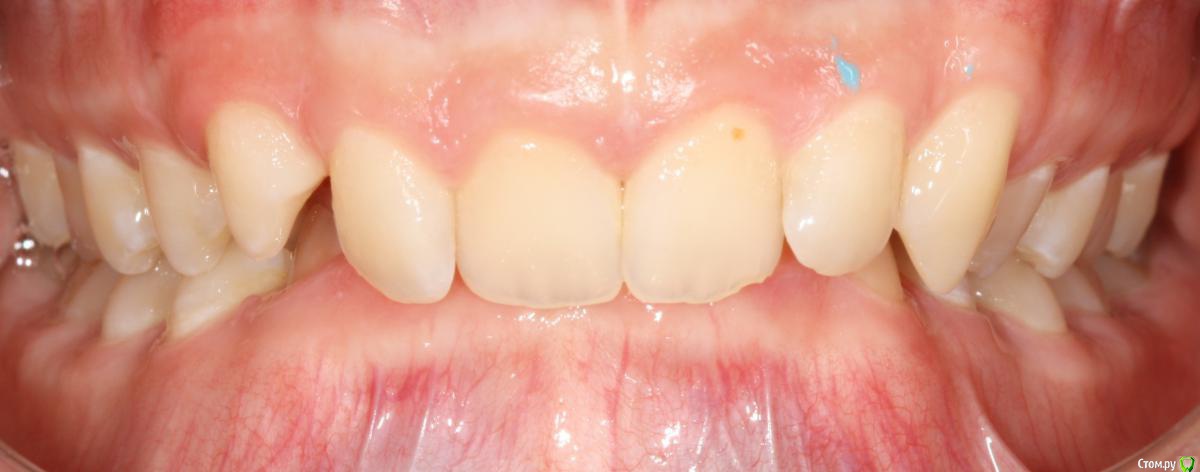

Opdihatop Опубликовано 24 октября, 2017 Поделиться Опубликовано 24 октября, 2017 И еще раз здравствуйте! Сразу хочу презентовать еще одного мальчика. Лично я такого еще не видел, а потому хочу понять, что тут делать. Думаю, невооруженным взглядом видно гипертонус и гиперплазию массетеров и гиперплазию углов н/ч из-за этого. Из-за чего это может быть и что тут делать? Как расслабить и что вообще делать с мышцами? Слать ли на сцинтиграфию (мало ли, может рост продолжается)? Есть ли шанс повысить прикус или такие мышцы все равно вколотят? Члх или нет? Заранее спасибо! Ссылка на комментарий

krokomot Опубликовано 24 октября, 2017 Поделиться Опубликовано 24 октября, 2017 Ботокс хорошо расслабляет, в данной ситуации, следует дифференцировать от остеодисплазии, херувизма. 1 Ссылка на комментарий

Brigita Опубликовано 25 октября, 2017 Поделиться Опубликовано 25 октября, 2017 (изменено) дифференцировать от остеодисплазии, херувизма.точно не херувизм. там в полости рта другая картина совсем, а по поводу дисплазии - она чаще односторонняя, может быть.... Изменено 25 октября, 2017 пользователем Brigita Ссылка на комментарий